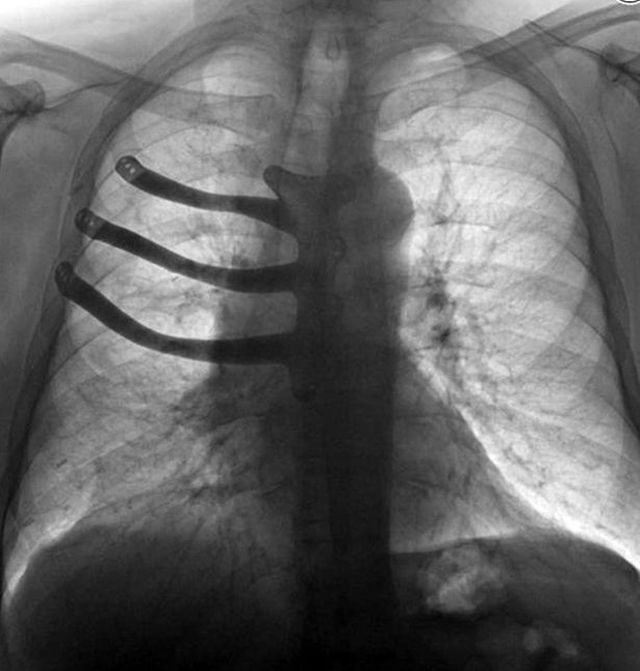

71-летний житель Британии Питер Маггс страдал от прогрессировавшего рака. Из-за болезни он лишился трех ребер и части грудной кости. Огромная опухоль распространилась на грудную клетку, поэтому некоторые кости пришлось удалить. Но врачам удалось спасти жизнь мужчины. Они напечатали новую грудину из титана.

Обычно в подобных случаях принято использовать цементные протезы. Однако медики смогли создать для Питера более прочную и точную конструкцию. Они спроектировали модель протеза и заказали ее распечатку у специализирующейся компании. Чтобы имплант был надежнее, его выполнили из титанового сплава. Операция увенчалась успехом. Пациент постепенно приходит в норму. Врачи отметили, что с таким подходом время операции уменьшается на пару часов, поскольку некоторые приготовления проходят быстрее. Кроме того, титановые импланты меньше подвергаются деформациям и сдвигам, а крепятся к костям они намного проще.